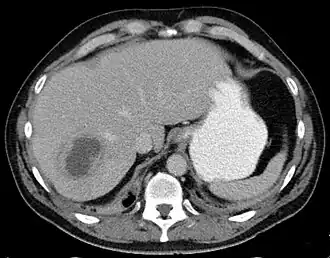

![]() Absceso hepático en la imagen axial de TAC: una lesión hipodensa en el hígado con realce periférico. | ||

En el ultrasonido se mostrará una masa quística en el hígado que tiende a ser septado o bien con características homogéneas. Si se hace una tomografía axial computarizada (TAC), se apreciará una masa hipodensa (oscura) con bordes precisos.[10] La aspiración percutánea del absceso y su cultivo microbiológico es esencial para el tratamiento adecuado y el drenaje del absceso. Con frecuencia se instala un catéter de drenaje, en especial para pacientes con abscesos complejos o que contengan fluido muy espeso. Los abscesos múltiples son comunes en pacientes inmunosuprimidos y se debe considerar varios organismos etiológicos, incluyendo una candidiasis.

La radiografía es la técnica más fidedigna para diagnosticar los abscesos hepáticos: la ecografía, la tomografía axial computarizada y, de encontrarse disponible, las gammagrafías con leucocitos marcados con indio o con galio radioactivos y la resonancia magnética.